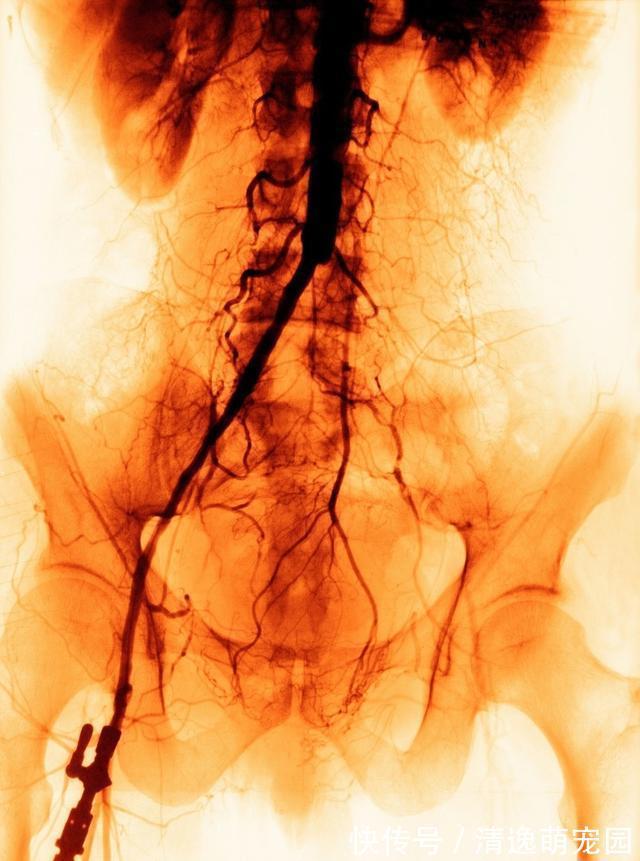

凌晨 2 点,距患者疼痛发作已 11 小时,患者右下肢疼痛复现。留观室值班医生,查看病人,发现右下肢膝盖平面以下明显缺血表现,股动脉、腘动脉、足背动脉、胫后动脉未触及。考虑急性右下肢动脉栓塞可能,遂查 CTA,见腹主动脉瘤伴附壁血栓形成,右髂总动脉分叉处以下髂外动脉、股动脉不显影,考虑右髂动脉分叉处骑跨血栓栓塞,请血管外科紧急会诊。

血管外科会诊后,于凌晨 3 点急诊行右股动脉切开,逆行、顺行取栓,取出髂动脉、下肢动脉内大量血栓,见近远侧喷血良好后,缝合股动脉切口。术后送ICU,最终因多脏器衰竭死亡术毕,送 ICU 重症监护。入室时见有下肢明显肿胀,肢端血供差,股动脉搏动可及,腘动脉弱,足背动脉未及。尿量减少,并出现肌红蛋白尿,血钾高,肌酸激酶严重升高。经过利尿、控制血钾等处理,肾功能仍迅速恶化,无尿,遂予 CRRT。室速、室颤发作,予抢救成功。小腿迅速肿胀发硬,出现张力性水泡。考虑缺血后再灌注损伤、骨筋膜室综合征。予骨筋膜切开减压。后病人病情持续恶化,建议行右下肢截肢,未行。发病第 3 天,病人多脏器衰竭死亡。下面带大家正确认识急性下肢动脉栓塞什么是动脉栓塞? 所谓动脉栓塞,一般都是急性发作的,来源于心脏或动脉壁脱落的血栓或粥样斑块等栓子随血流向远端动 脉流动,卡在口径比栓子小的动脉并堵塞管腔,发生肢体、器官和组织的缺血和坏死。